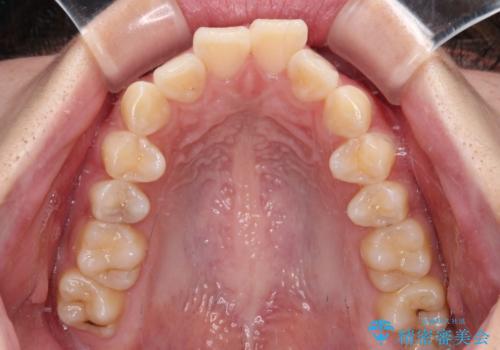

口元が出ているのを改善したい。 クリアブラケットによる抜歯矯正

- 前歯部のデコボコと口元が出ているのが気になるとのことで来院された患者様です。

口元の突出感の解消と、このままデコボコを解消するとさらに出っ歯傾向になってしまうことを考慮し、上下左右の小臼歯を抜歯しクリアブラケットにて矯正していくこととしました。